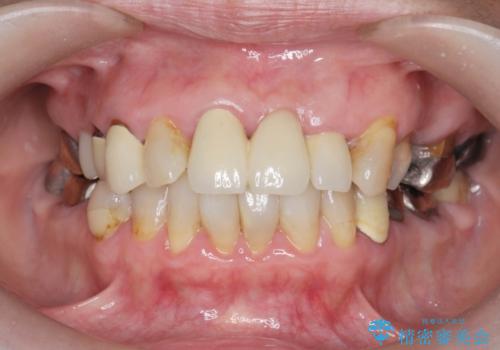

[メタルフリー] 虫歯・銀歯だらけの口腔内を全顎治療

![[メタルフリー] 虫歯・銀歯だらけの口腔内を全顎治療の症例 治療前](https://seimitsushinbi.jp/wp/wp-content/uploads/2025/03/e26a9887bc6905a2f0f51f5772b5ac9c-500x350.jpg?v=1741918285)

![[メタルフリー] 虫歯・銀歯だらけの口腔内を全顎治療の症例 治療後](https://seimitsushinbi.jp/wp/wp-content/uploads/2025/03/530cf6cca6451bc106a9fb69dd58908a-500x350.jpg?v=1741918343)